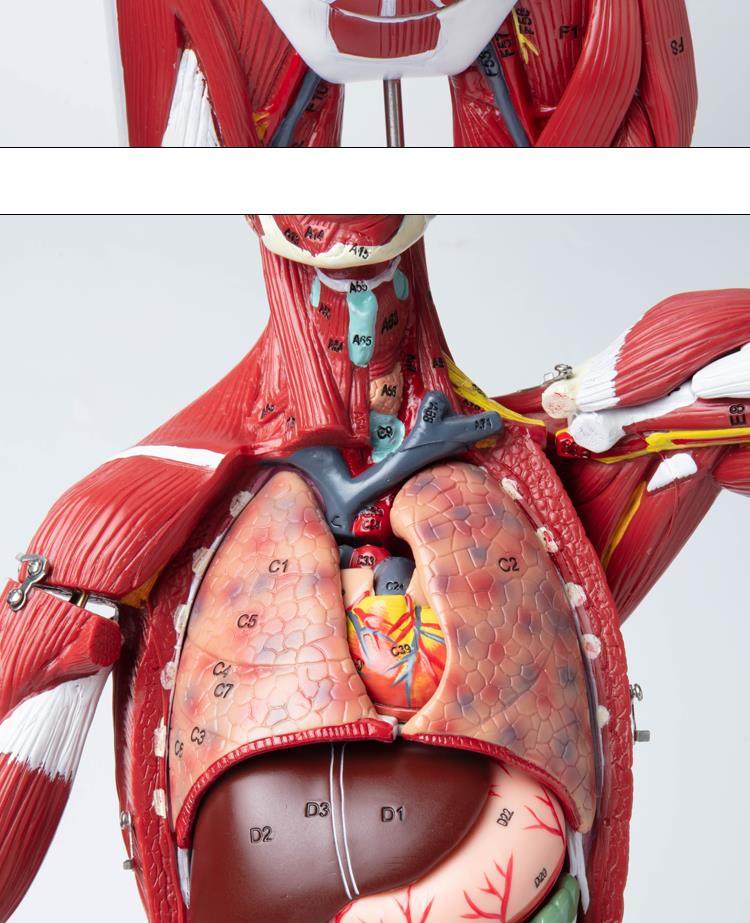

Human Body Muscle Internal Organ Disassembly Anatomy Structure Model Tissue Exercise Artificial Medical Teaching Aids

| Color Classification | 85 Human Muscle Internal Organs Removable Organ,50cm Muscle Model |